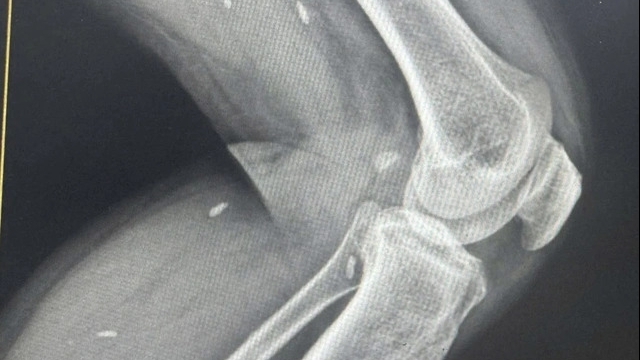

![]() |

| Một trường hợp bị mất thị lực một bên mắt do tiêm filler tại cơ sở thẩm mỹ chui |